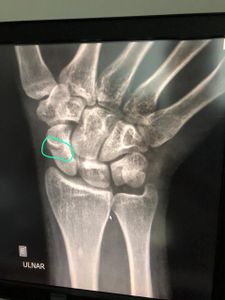

Olá. Sou o Rafael, criei  esta vaquinha para conseguir sair das dívidas ocasionadas pela pandemia. Sou casado, moro de aluguel, faço faculdade junto a minha esposa. Tenho emprego fixo, mas minha esposa atualmente trabalha com diárias. Recentemente sofri um acidente e estou sem trabalhar, na queda fraturei o terço médio do escafoide. Já entramos em cheque especial e empréstimos. VOU PRECISAR PASSAR POR CIRURGIA, e o SUS está sem previsão de retorno de pequenas cirurgias, pois o osso não colou somente com a tala. Preciso fazer este procedimento particular o quanto antes para evitar sequelas.  Estamos vivendo de doações e ajudas para sobreviver. Peço sua ajuda para que possamos pagar nossas dívidas e para que possamos melhorar nossa situação.